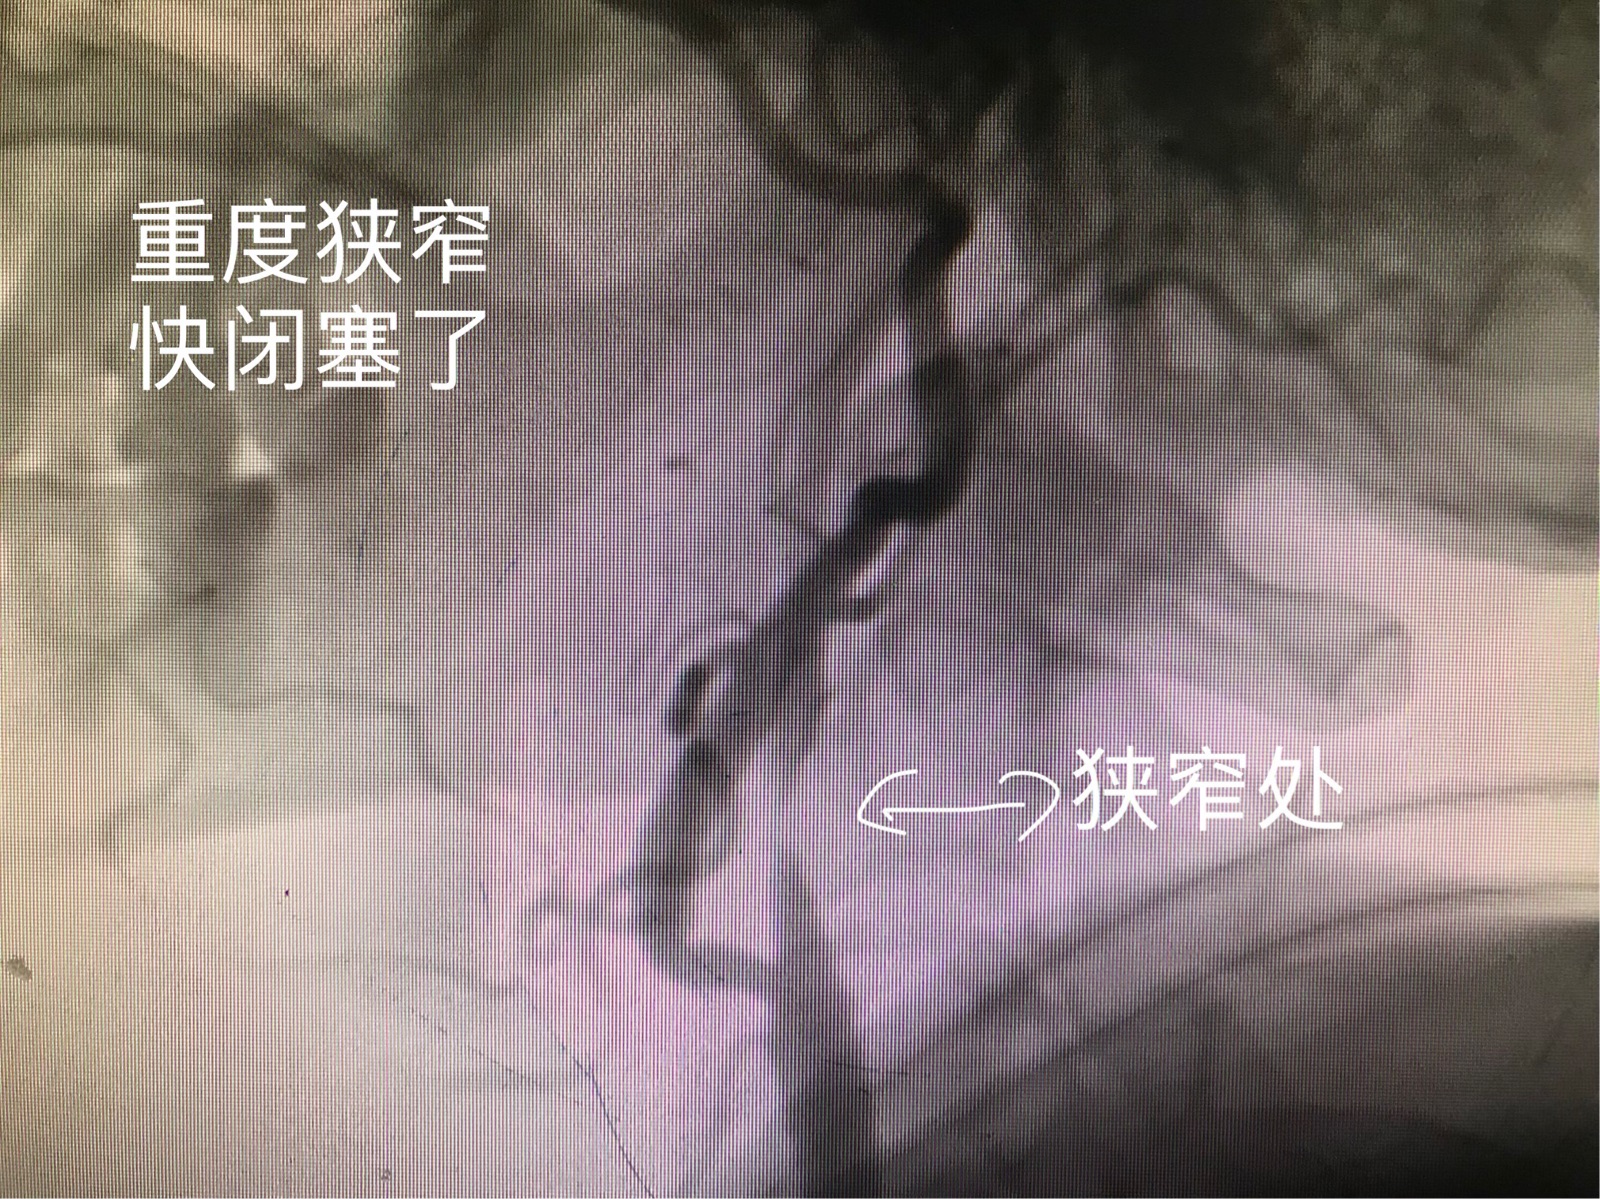

颈动脉快要闭塞了

术前造影,脑供血较差